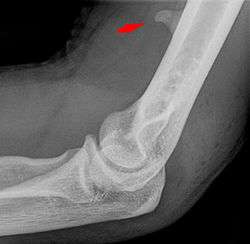

Small supracondylar process seen on a lateral radiograph of the elbow

The supracondylar process of the humerus is a bony projection on the anteromedial aspect of the upper arm bone (humerus), about 5 cm above the medial epicondyle. It is directed downward, forward and medially pointing to the medial epicondyle. It is an anatomical variation which occurs in about one percent of all people. A fibrous band, Struthers ligament, may connect this process to the medial epicondyle.